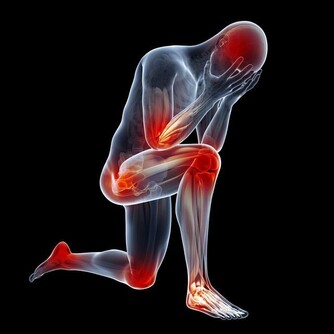

關節炎是一種影響所有年齡段人群的常見病症,它的症狀包括運動受限制、關節疼痛、關節出現炎症,以及受影響區域的皮膚紅腫發燙。